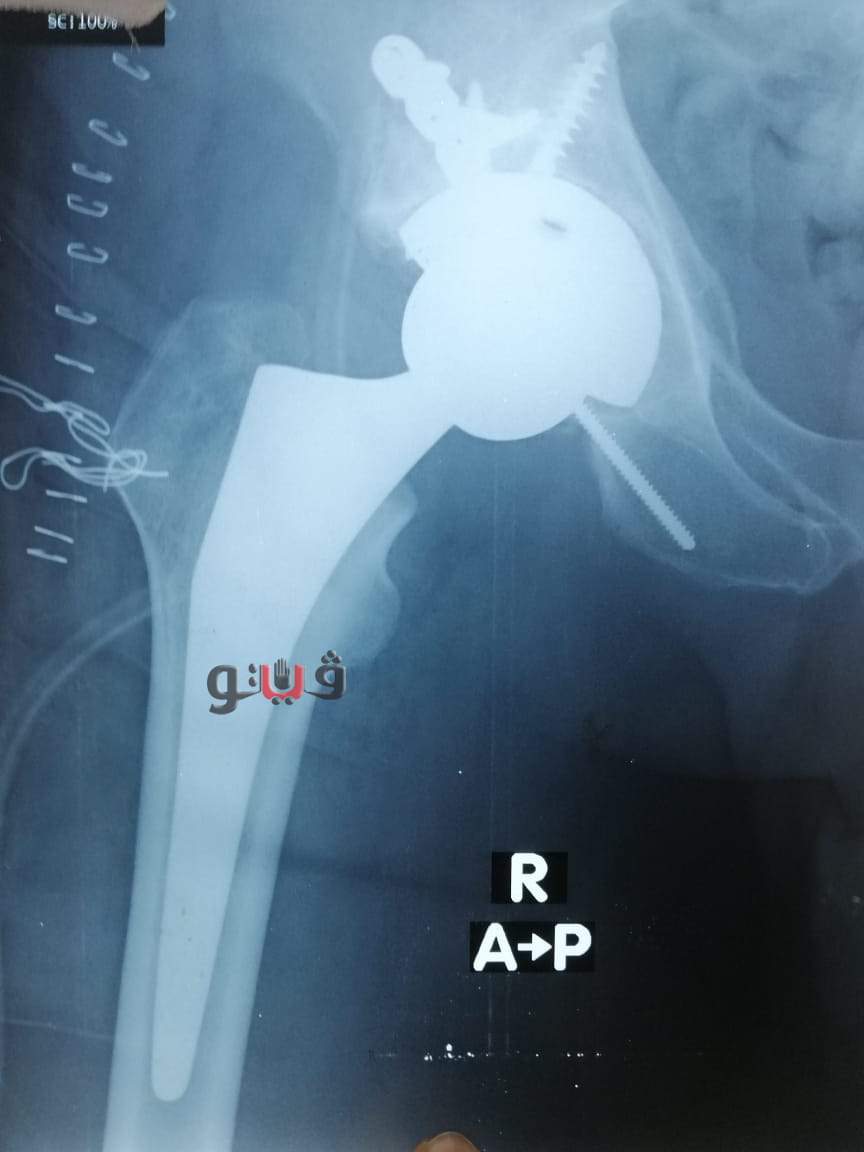

وكان المريض ضمن الحالات الحرجة لقوائم الإنتظار حيث تمكن الفريق الطبى من اجراء استبدال مفصل فخذ صناعي كامل حيث استغرقت العمليه حوالي ثلاث ساعات وتعد هذه العملية من الجراحات المتقدمة ذات المهارة الخاصة.

كما اطمأن وكيل الصحة على صحة المريض حيث عاد الي حالته الطبيعيه وبحالة مستقرة.